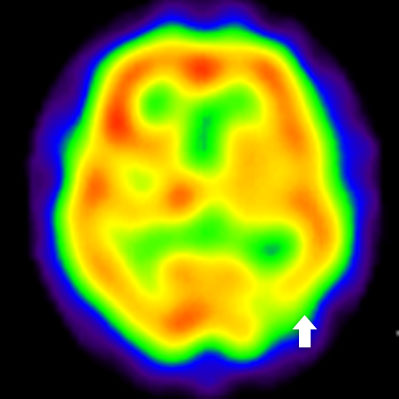

2) 脳血流シンチグラフィ